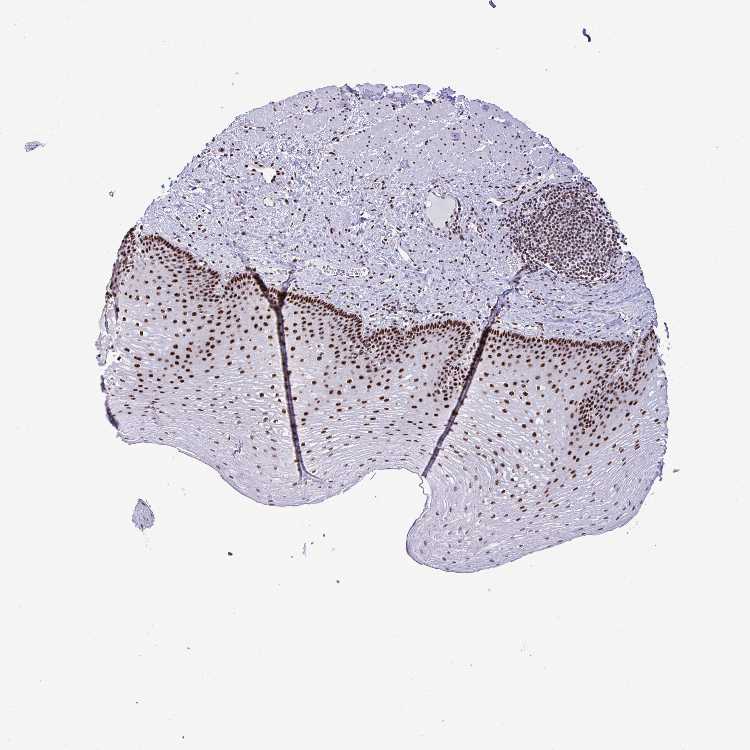

ESOPHAGUS - Antibody stainingi

Antibody staining in the annotated cell types in the current human tissue is reported as not detected, low, medium, or high, based on conventional immunohistochemistry profiling in selected tissues. This score is based on the combination of the staining intensity and fraction of stained cells.

Each image is clickable and will lead to virtual microscopy that enables deeper exploration of all samples and also displays staining intensity scores, fraction scores and subcellular localization as well as patient and tissue information for each sample.

Antibody HPA060760

Squamous epithelial cells High